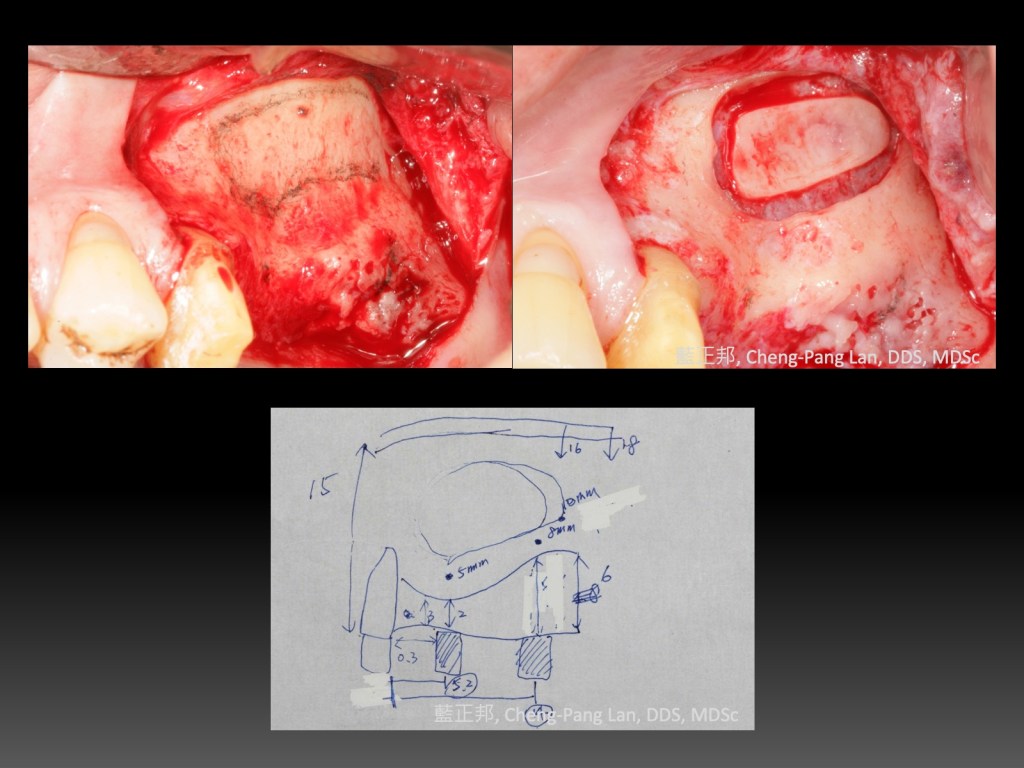

手術模擬

以前多顆牙的補骨手術,都看著電腦斷層,藉由三視圖,腦中重組手術可能看到的畫面,這個方式很消耗腦力,手術臨場感也低。

之前台大學弟拿3D列印的齒槽骨,找我討論手術計畫,雖然我年資比較深,反倒是自己學到很多。於是也試著把案例,3D列印出來,做手術模擬。

拿任何可塑形的軟蠟、黏土,當作骨粉,先堆出理想植牙的骨量,拿消毒紙,或接近再生膜性質的替代品,模擬裁剪不可吸收再生膜。

這順序很重要。以前手術比較急躁,先剪再生膜,放骨粉後,才發現再生膜大小不夠。能事先手術模擬,紙片可以隨意挑選大小,無限制地剪裁,再送進消毒鍋,手術當天就可以照這樣剪。甚至,拿過期的再生膜,更可以模擬內部鈦金屬支架的位置,事先彎曲好,放在3D列印材料上,研究釘子的位置。

我的YouTube影片裡有提到,不可吸收再生膜需要「Passive Fit」,減少後續併發症。如果不夠passive fit,金屬支架的內部應力一多,釘子可能會鬆脫,造成補骨區域「固定」不足,骨生長就不是很順利了。

手術模擬的同時,打開教科書,兩本Urban‘s Vertical Ridge AugmentationGrunder’s Implant in the Esthetic Zone,看看大師們怎麼擺放再生膜,讓自己更貼近他們一點。

手術模擬的同時,也請跟刀助理,一起準備手術流程,尤其是釘釘子的手勢與節奏,讓團隊提早進入手術狀態。

經過如此的演練,我發現到,手術前的焦慮感降低不少,同時,實際手術時間更快,手術後的踏實感也有增加喔~~

回顧還發現,其實第一次做開窗就用手繪圖了,有興趣如何準備開窗手術的初學者,我寫了一篇在這裡